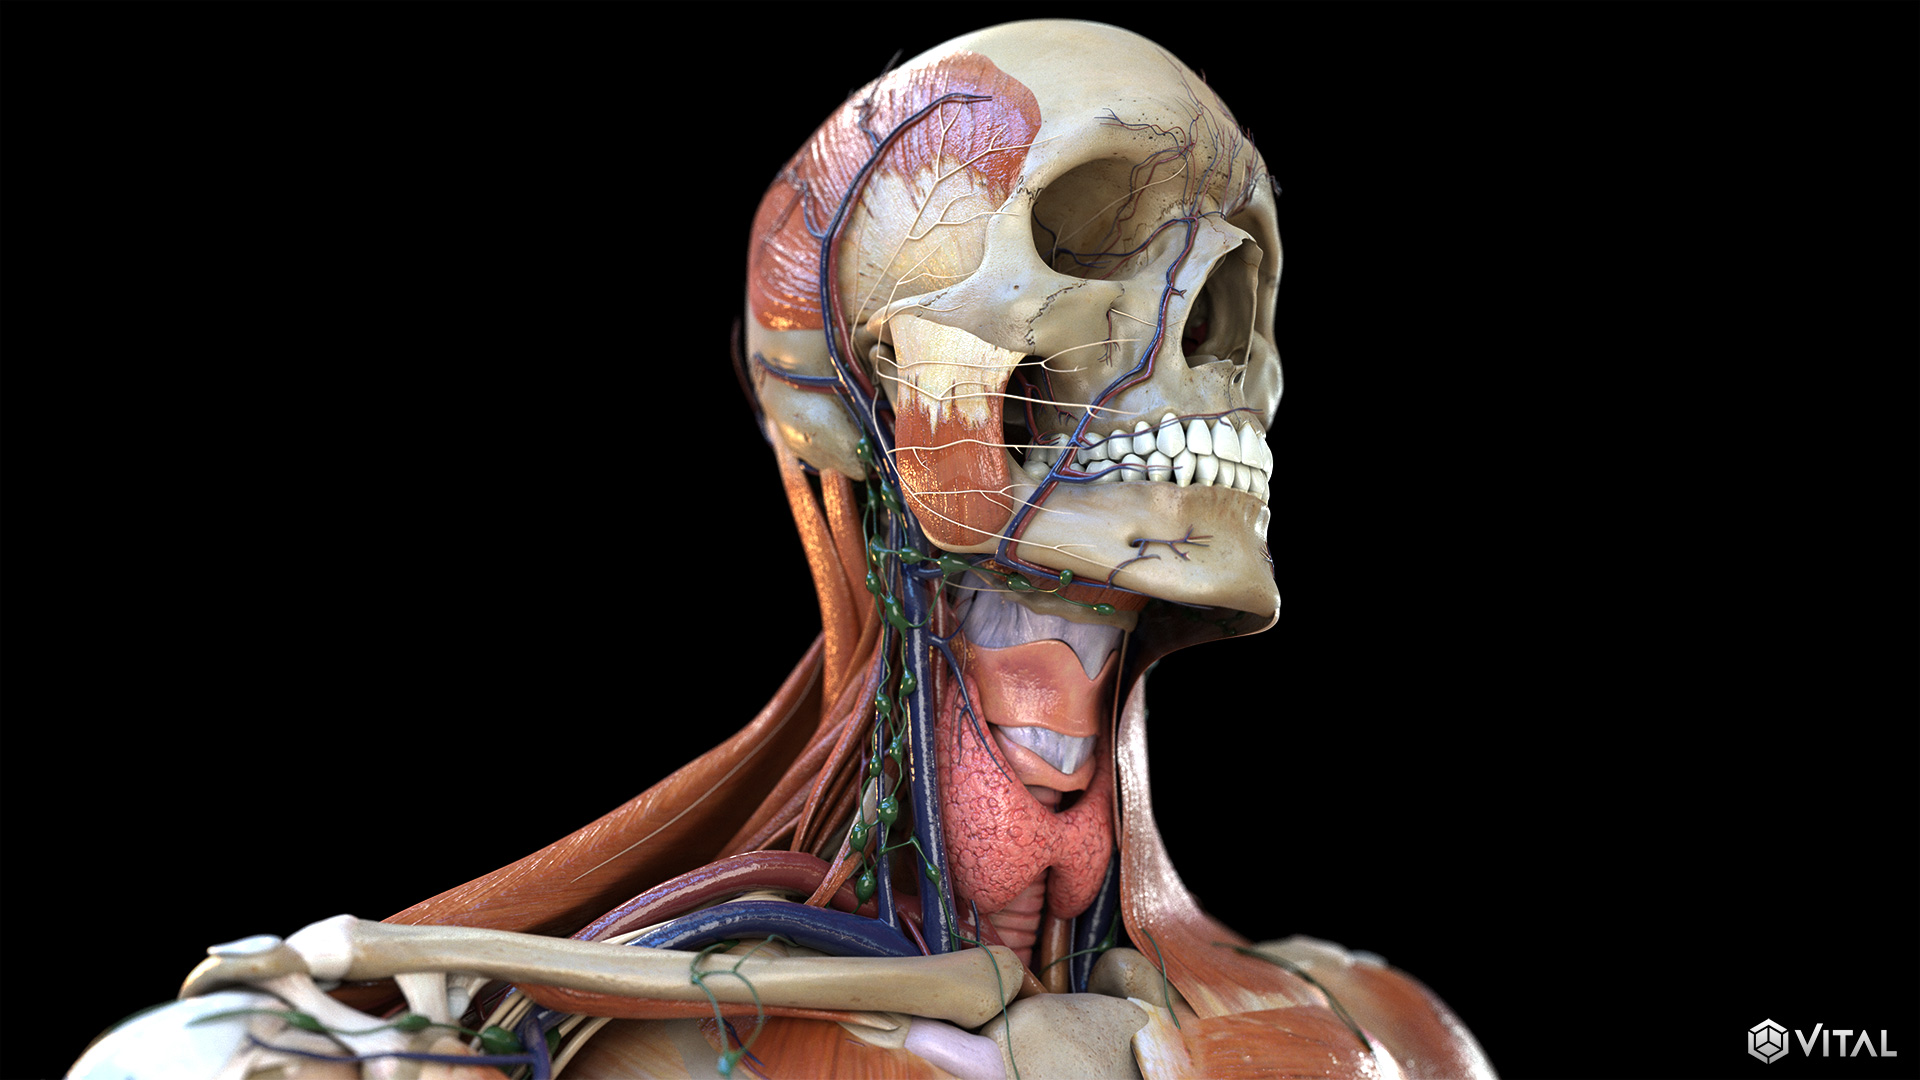

Medical

Vital and UET collaborate to support several clients throughout the medical industry. Together, we provide illustrations, animations, and trial exhibits to help depict complex anatomy and medical procedures clearly and precisely. We’re able to create an immersive, easy to understand learning experience, by combining real footage, such as captured ultrasounds, with correlating high fidelity 3D animation.